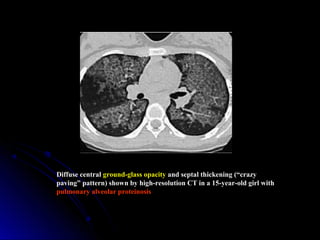

Diffuse central ground-glass opacity and septal thickening (“crazy

paving” pattern) shown by high-resolution CT in a 15-year-old girl with

pulmonary alveolar proteinosis